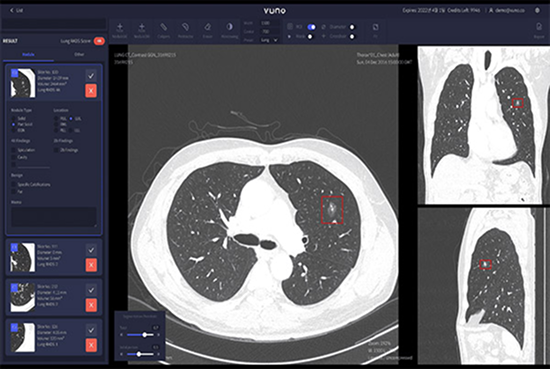

VUNO Med-LungCT’s competitive edge is about its performance. An AI-based product that assists lung diseases diagnosis, it also provides data on nodules’ size, volume, and location.

Results are integrated with PACS in the format of GSPS objects, which ensures great user convenience.

• Provides volumetric data of nodules

• Provides a mask feature to detect part-solid nodules (Overall, Ground-glass, Solid Part)